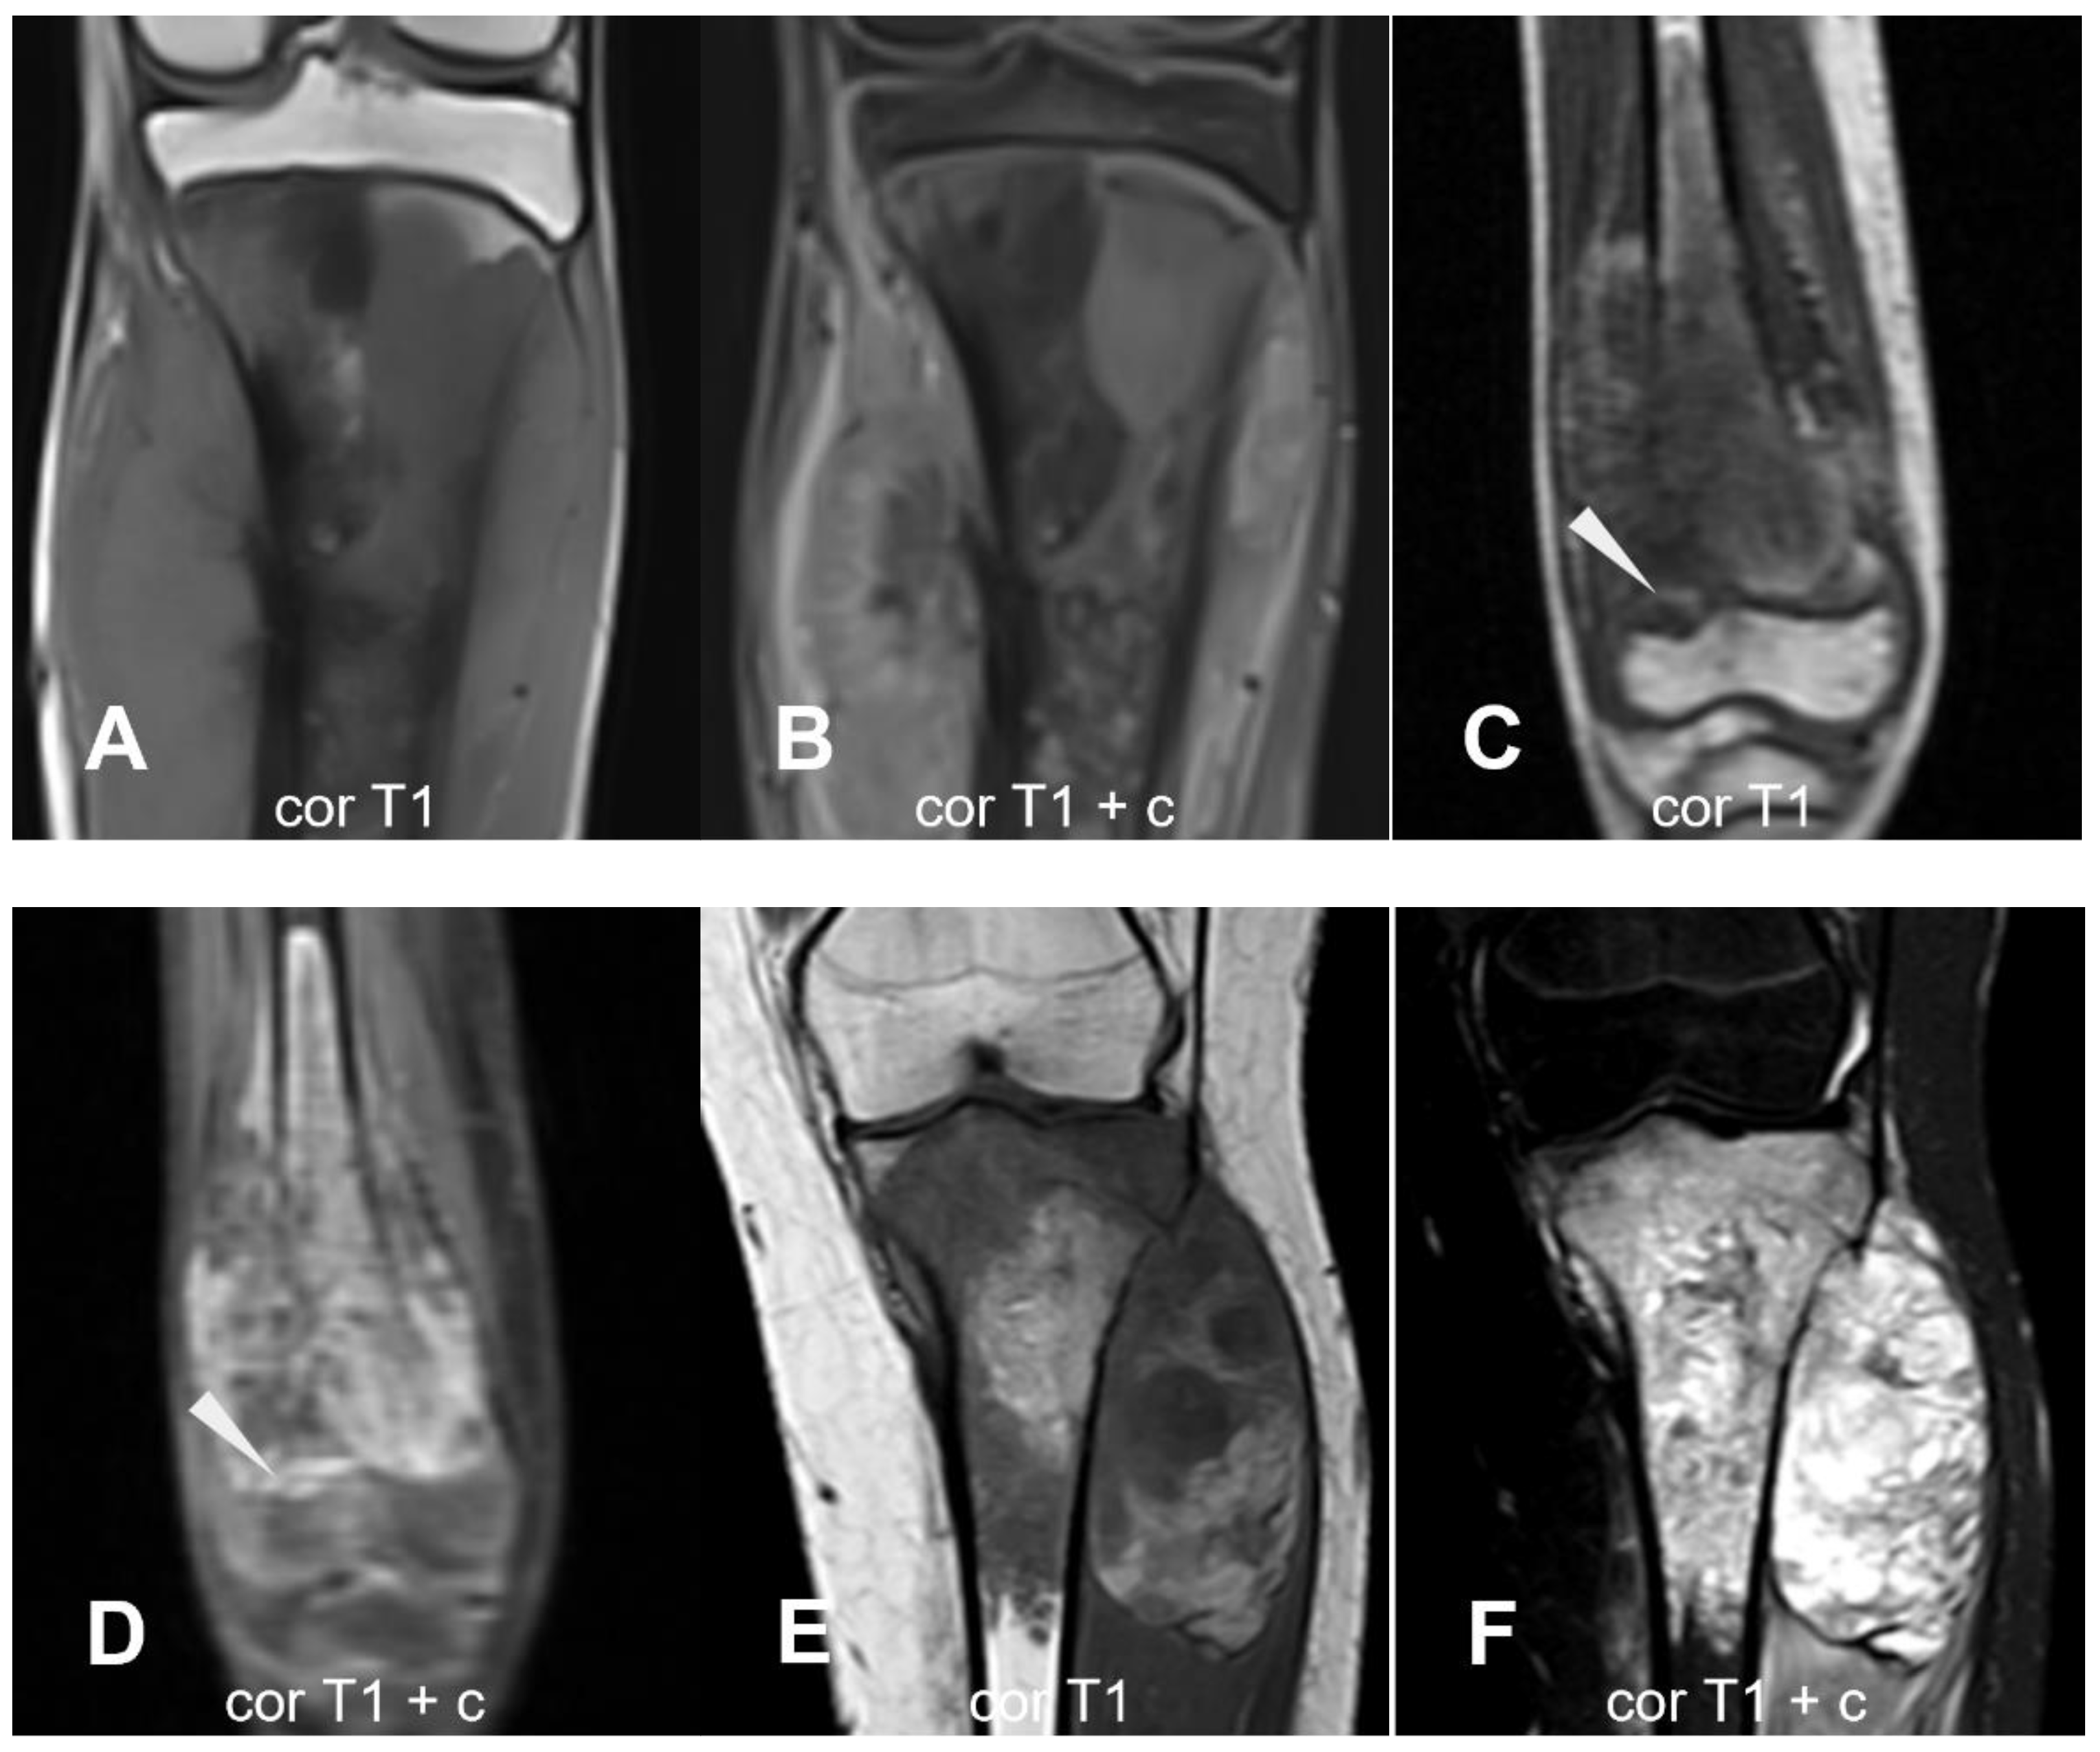

3.1.3. Teleangectatic Osteosarcoma

3.2.1. Parosteal Osteosarcoma